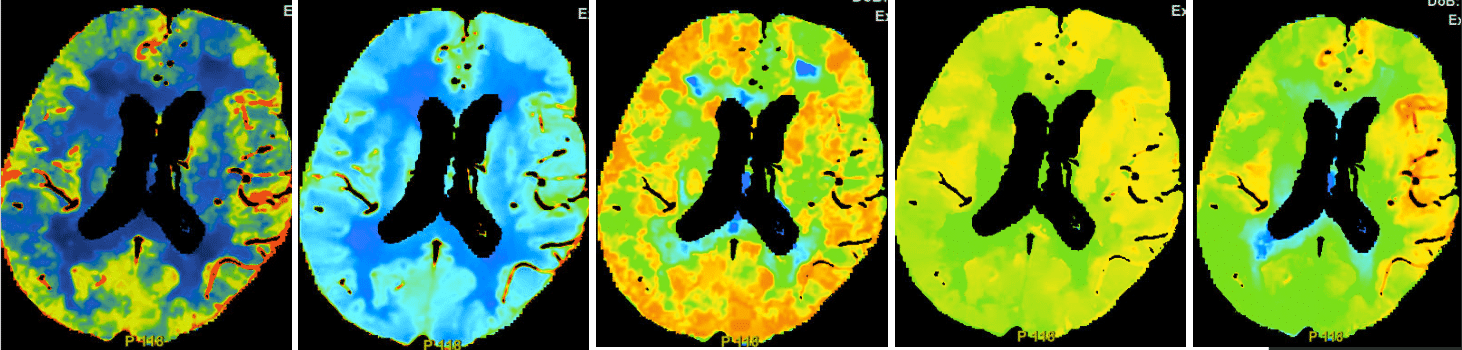

CTP(2025-7-9 09:02 本院):序列依次为CBF、CBV、MTT、TTP、TMAX,所见双侧大脑半球颜色标记基本对称,未见明显差异。